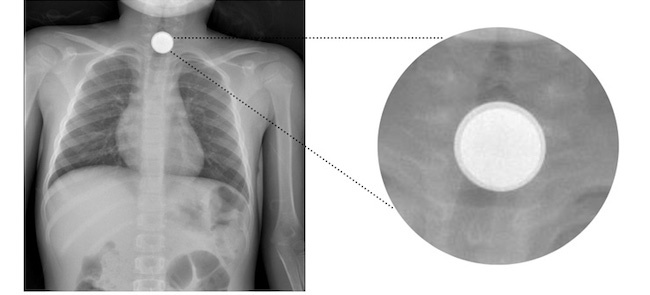

To discard multiple impacted objects, another anteroposterior CTA X-ray was obtained observing the persistence of the foreign body, but this time, only two superimposed objects were seen (Fig. 2). The patient was then taken to the operating room. During the flexible esophagoscopy, 2 coins (2 and 5 cents €) were found stacked at the level of the upper esophageal sphincter, both were removed without difficulty. The patient had an uneventful postoperative recovery and was discharged 12 hours after the procedure. There have been no long-term complications.